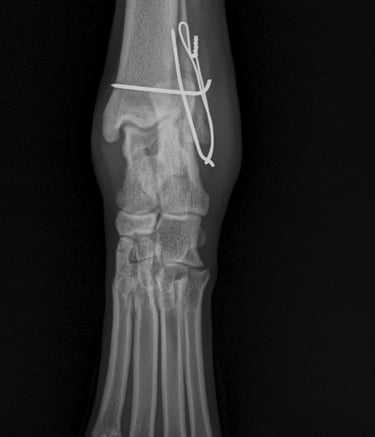

Buddy recovered well and in 4 weeks post op Xrays we could see that the fracture was healing well (Fig 5 and 6).

Fig. 6

Fig. 5